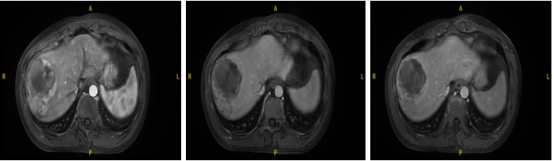

腹部MRI(2023-02-21): 肝右叶近膈顶及肝右叶下角处MT(恶性肿瘤);双肾小囊肿。

经评估对比,用药后肿瘤稳定,对比之前肿瘤活性减弱,肿瘤边界清晰,具备手术条件。

用药后腹部MRI(2023-4-3):肝右叶近膈顶及肝右叶下角处MT,较2023-02-21片病灶部分坏死;双肾小囊肿;肝门部及腹膜后稍大淋巴结。